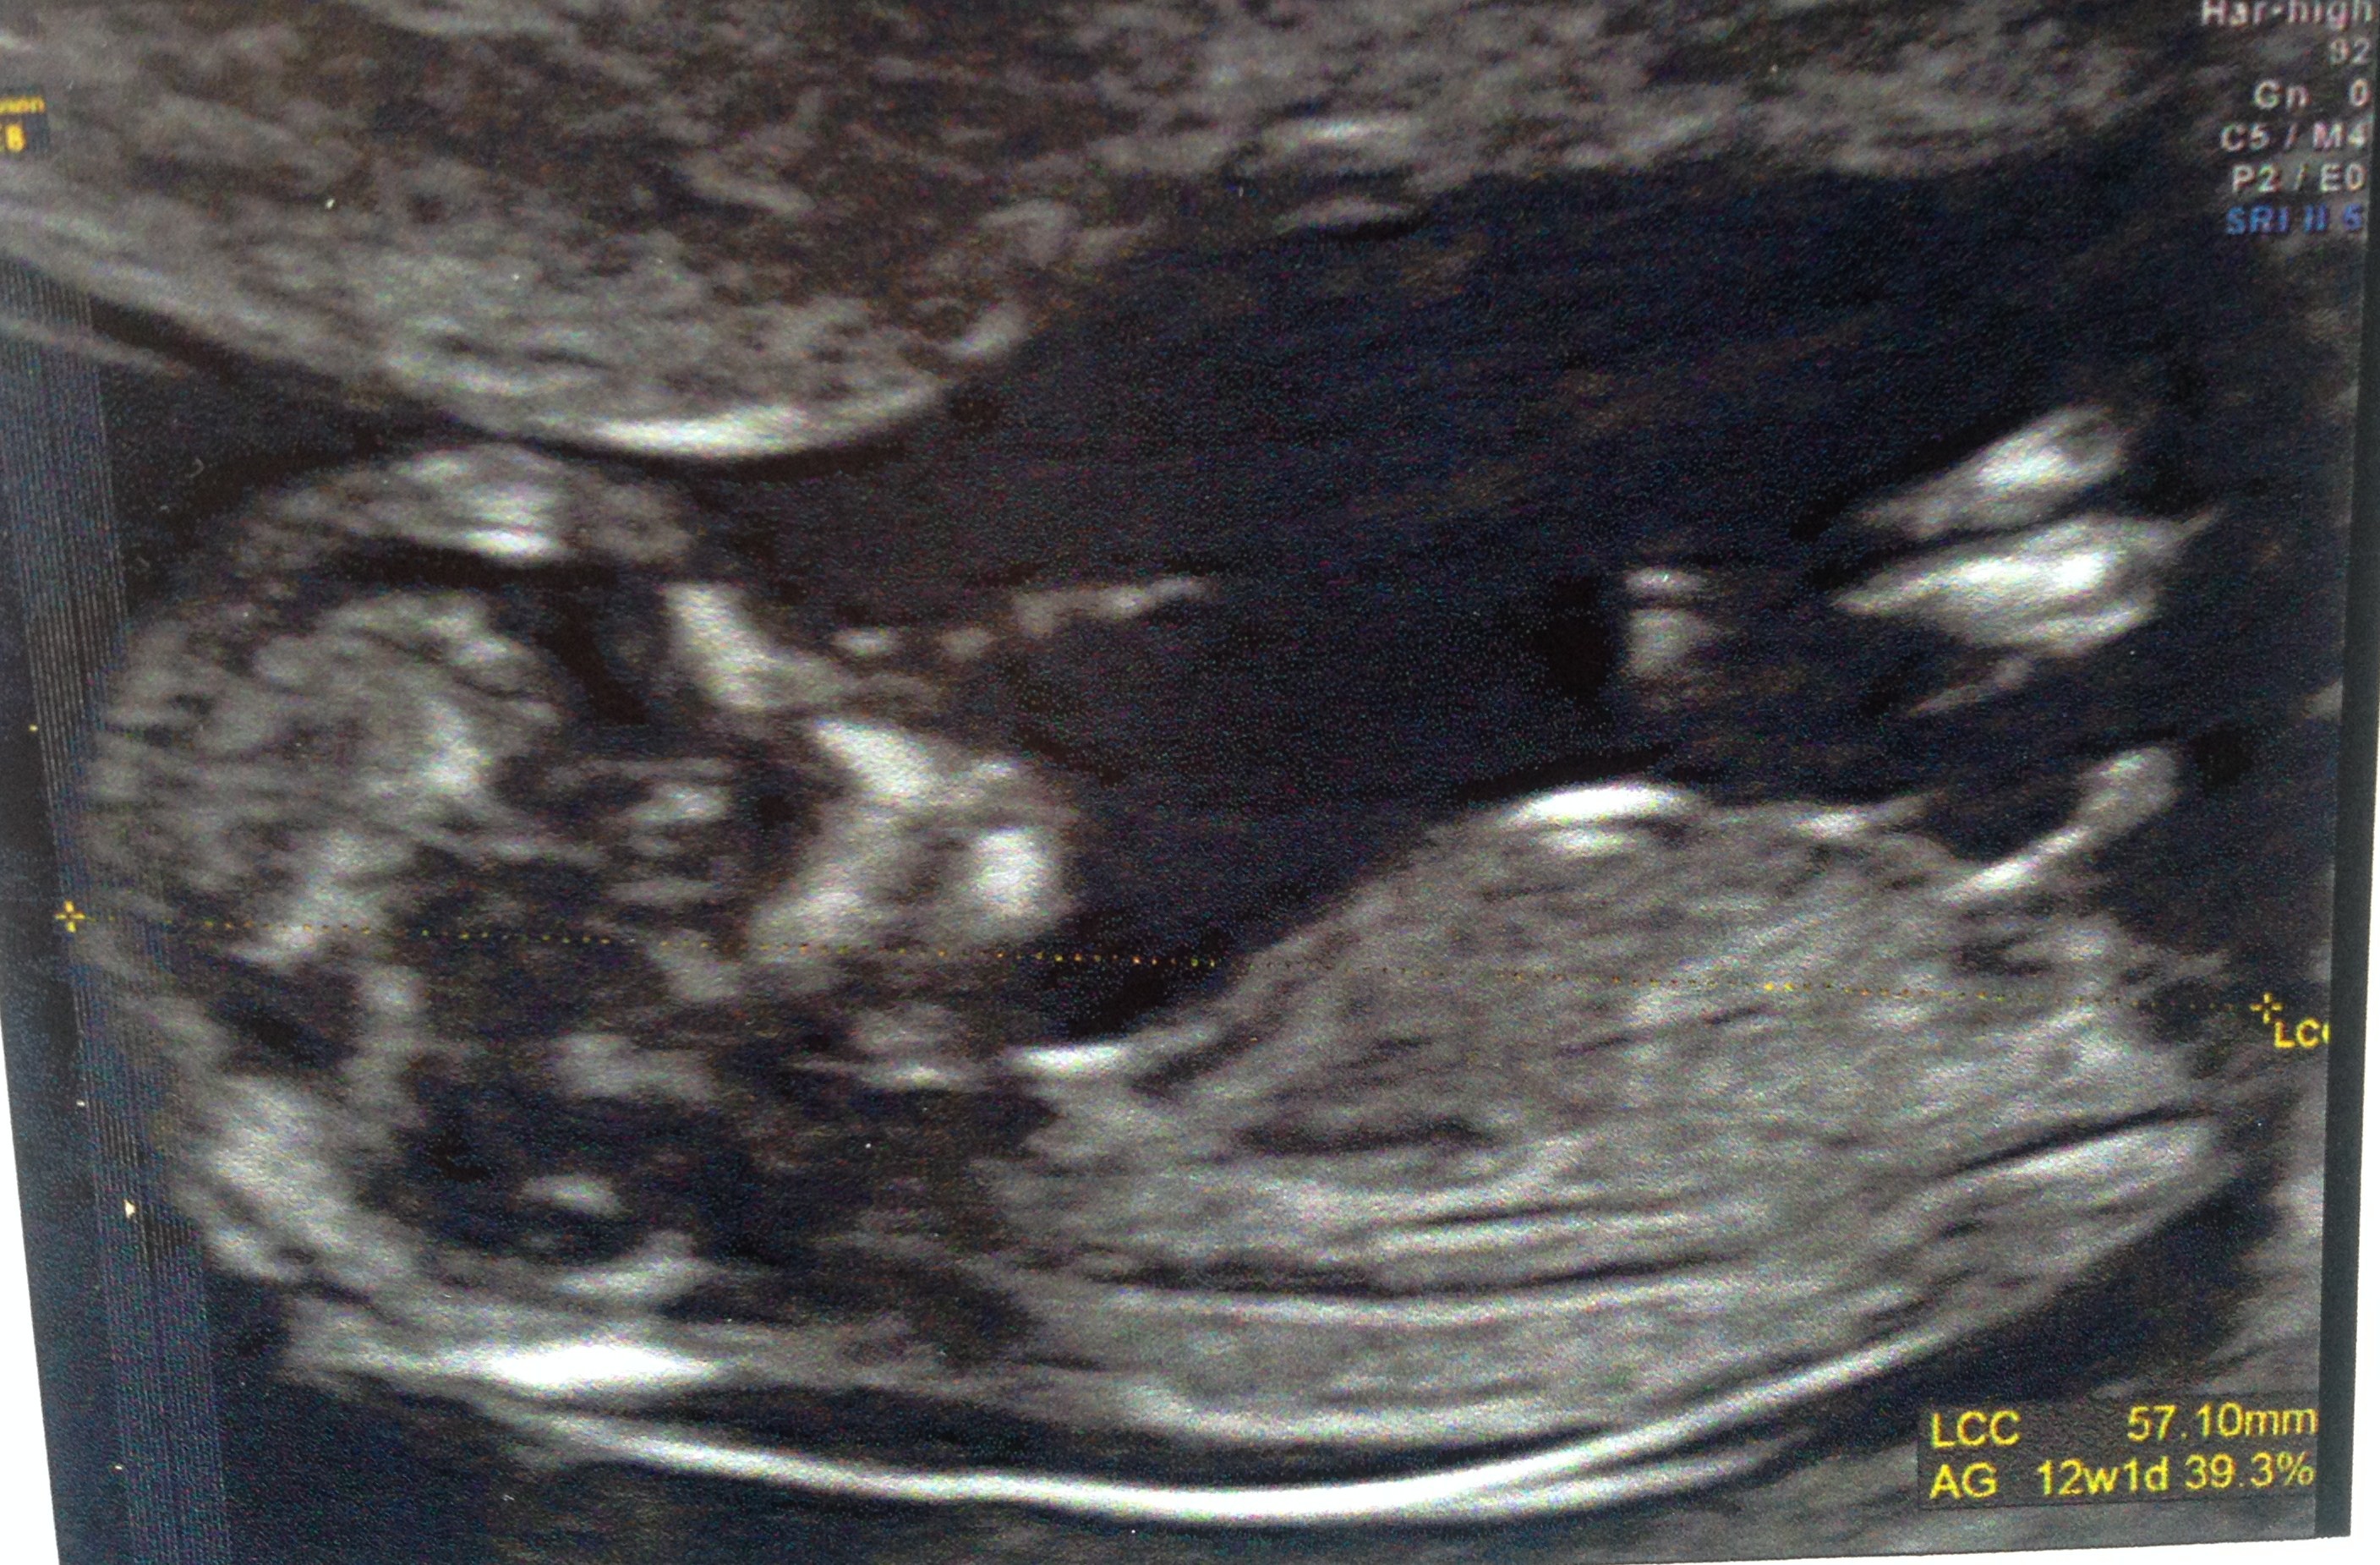

The least interesting videos on youtube see Youtube ToS and Google privacy policyYoutube ToS and Google privacy policy · Essai bébé 4et au cycle 2 le 05/08 Pds 11/08 1636 ui Je suis né le 19 avril à 2h, et je m'appel Adam Haut Marionette30 Alors aur je suis désolée aussi mais je vois carrement une fille et ça à l'air bien flagrant car le tubercule est incliné vers le bas et je ne pense pas qu'il va remonter ça ressemble beaucoup à ma fille;) Je suis actuellement enceinte de 13sa (mon 1er bébé), voici une photo de la dernière écho de mon petit trésor prise à 12 sa 3

Sur cette photo, le bébé est bien allongé sur le dos, mais le tubercule semble s'élever C'est un enfant petit !Quand le tubercule se transforme?Il est possible sous certaines conditions de déterminer le sexe du bébé dès 12 SA révolus, en fonction de l'orientation du tubercule génital et en prenant les mesures des angles qu'il

· En effet, le manioc contient une substance toxique, l'acide cyanhydrique Il doit être obligatoirement consommé cuit Pour le consommer, il faut donc le peler, le rincer, le découper et le cuire longuement à l'eau bouillante (40 minutes environ) ou à la vapeur (presque une heure) Par ailleurs, il ne faut pas consommer l'eau de cuisson qui contient alors les substances toxiques · La tuberculose pédiatrique est un problème de santé de bébé devenu rare en raison de la vaccination, mais elle existe toujours et il est · Il y a certaines règles qui doivent être respectées pour que ce bourgeon ne bouge plus Être au moment de l'écho entre 12 SA et 13 SA et que la LCC de ton bébé soit supérieure ou égale à 6 cm Sachant que quand le bourgeon est fille, celui ci peut remonter jusqu'à 14 SA !

;) Voici une photo de l'écho pourque tu compares !Cette méthode repose sur l'observation du bourgeon génital de votre enfant (aussi appelé tubercule génital) Ce bourgeon est l'organe sexuel indéterminé de votre bébé, qui se transformera au cours du deuxième trimestre en pénis chez les garçons ou en clitoris chez les filles Mais au début de la grossesse, le bourgeon ne présente aucune différence · La gygy ne sait pas prononcer Pour un garçon Le tubercule pointe vers le haut et forme un angle de plus de 30° avec la base de la colonne vertébrale Pour une fille Un angle entre le dos du foetus et le tubercule génital inférieur à 10° en faveur d'une petite fille

· C'est son orientation qui renseigne sur le sexe de l'enfant", détaille le Dr Mironneau En effet, si à l'écran, le bourgeon génital a une orientation verticale alors le bébé à naître est certainement un garçon En revanche, si ce tubercule génital est horizontal alors l'enfant à venir est potentiellement une petite fille Mais, dans certains cas, le bourgeon génital se développeSelon l'angle d'inclinaison du bourgeon, vous pouvez deviner le sexe de bébé Pour un garçon Le tubercule pointe vers le haut et forme un angle de plus de 30° avec la base de la colonne vertébrale Pour une fille Un angle entre le dos du foetus et le tubercule génital inférieur à 10° en faveur d'une petite fille C'est à dire que le bourgeon génital suit l'axe de la colonne vertébrale, ilLe bébé sur cette image a un LCC assez élevé, plus de 70 mm, et la grossesse es Les techniques actuelles, notamment l'échographie, mais il faut quand même après s'adapter au fait que, ben voilà, ce ne sera pas une fille

Le tubercule génital fœtal est la conception des organes génitaux, on peut le dire Dans les garçons et les filles sont très semblables jusqu'à la 14e semaine et jusquelà, les médecins ne peuvent être absolument sûrs Cependant, des études plus approfondies sur le sujet ont abouti à la conclusion que, selon l'inclinaison du tubercule génital fœtal, on peut savoirSi le tubercule est perpendiculaire au corps alors c'est probablement un garçon!Le tubercule génital du bébé de gauche forme un angle de plus de 30 ° avec l'axe de la colonne vertébrale c'est donc sûrement un garçon Le bourgeon commence même à ressembler un peu à un pénis avec de petites bourses

Ainsi dans de bonnes conditions techniques (échographiste entrainé, échographe performant et adapté à l'échographie de grossesse, bon passage des ultrasons à travers la paroi maternelle, bonnes positions du foetus et surout terme de grossesse supérieur à 12,5 SA), le diagnostic du sexe foetal est possible dans plus de 90 % des cas au premier trimestre · Pour connaître le sexe de bébé avec l'échographie, on utilise la méthode du bourgeon Elle est fiable à 80/85% à ce stade de la grossesse, car le tubercule génital n'est pas encore complètement formé / développé · Les tubercules de Montgoméry quels rôles ontils au moment de l'allaitement ?